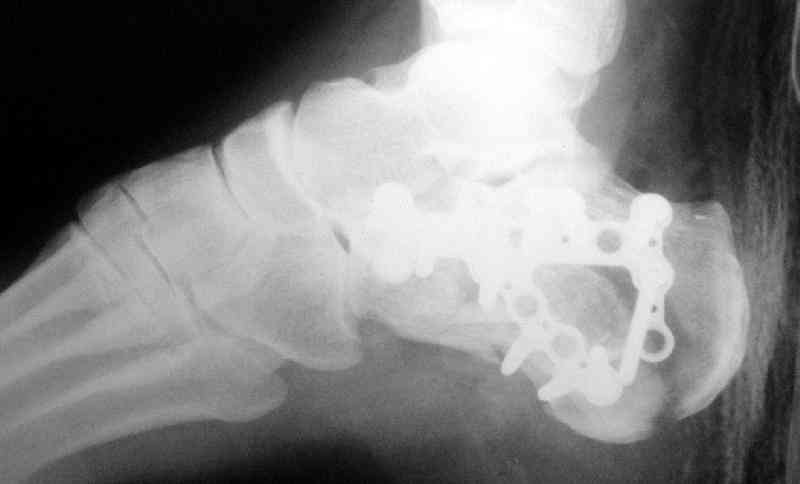

Пяточной пластиной

Открытый и закрытый способы лечения.